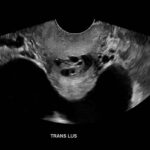

Ovarian hyperstimulation syndrome (OHSS) is a potentially life-threatening complication of assisted reproductive technology (ART). Here, we present the case report of a 30-year-old female undergoing infertility treatment who presented to the emergency department (ED) with nausea and vomiting, abdominal distention, and shortness of breath. On physical exam, she had notable ascites. Computed tomography (CT) of the abdomen and pelvis and pelvic ultrasound (US) revealed significant ascites and enlarged ovaries with multiple cysts. She was diagnosed with severe OHSS and admitted to obstetrics and gynecology (OBGYN) service for five days where she underwent intravenous (IV) hydration and paracentesis. This case report reviews the clinical presentation, categorization, management, and prevention of OHSS and provides examples of imaging findings consistent with the condition.